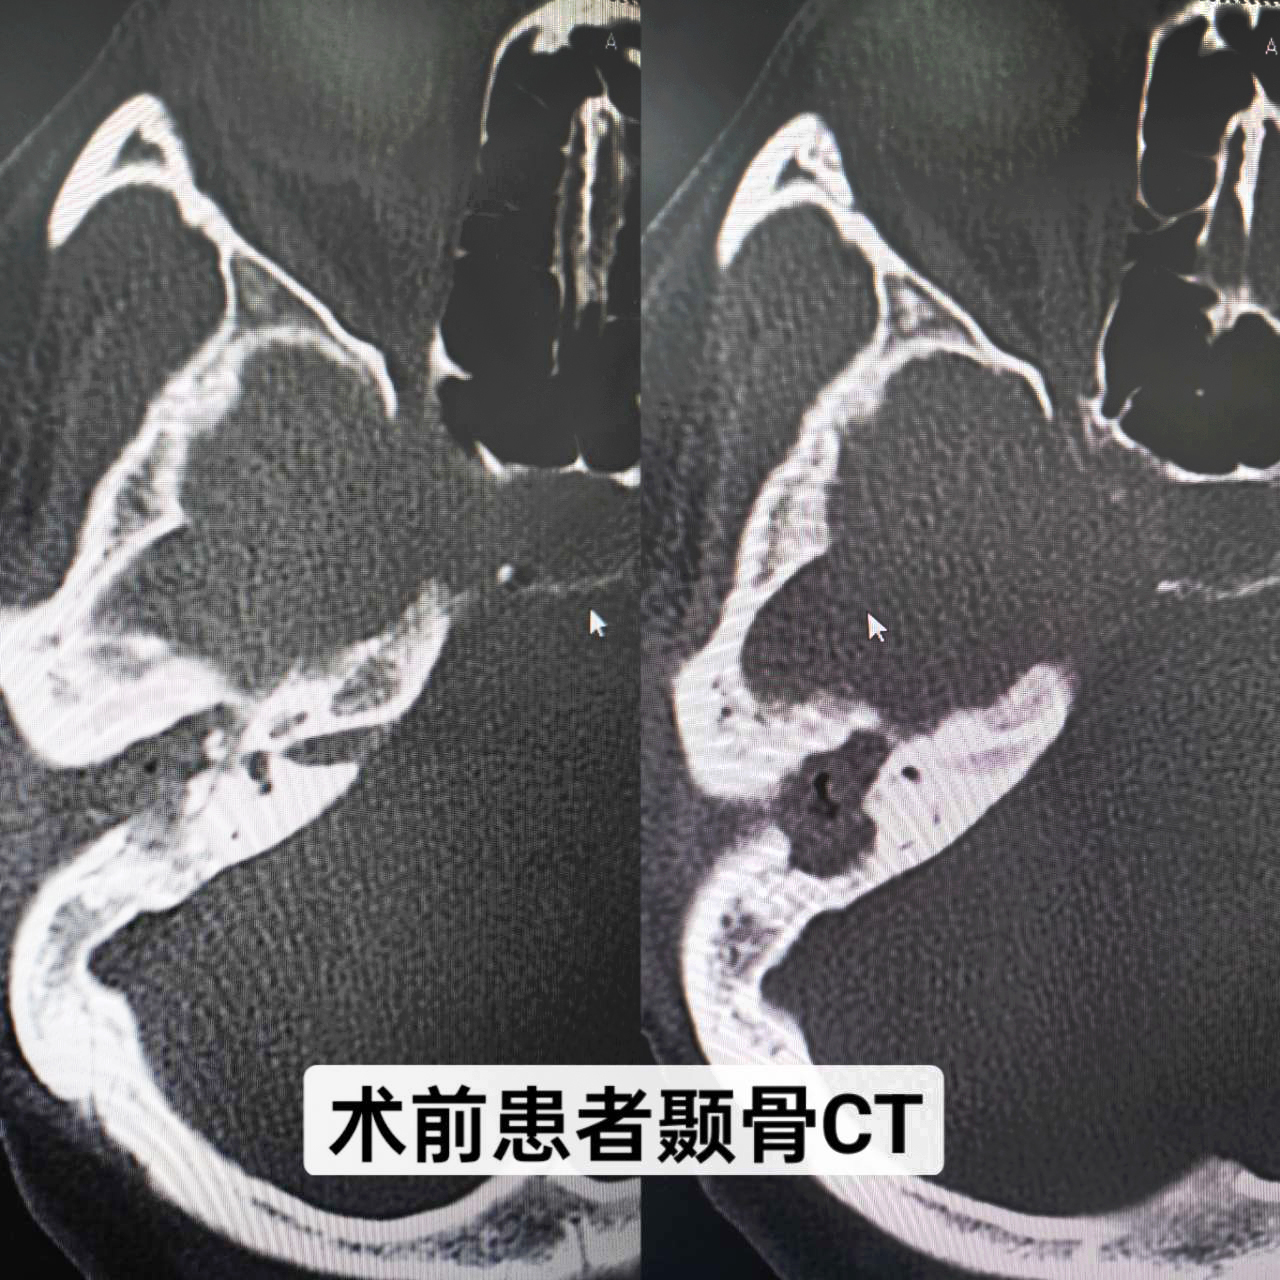

患者,女,34歲,幼兒時(shí)發(fā)生過(guò)中耳炎,經(jīng)治療后已明顯好轉(zhuǎn),但最近一個(gè)月反復(fù)右耳腫痛、流膿、流水,伴聽(tīng)力下降,嚴(yán)重影響生活,來(lái)我院就診。耳內(nèi)鏡示:右耳外耳道縮窄,肉芽組織及膿血性分泌物填充,鼓膜窺不及;顳骨CT示:右側(cè)中耳鼓室擴(kuò)大,見(jiàn)軟組織影填充并向外耳道延伸,右側(cè)聽(tīng)小骨骨質(zhì)吸收,形態(tài)小,部分聽(tīng)骨欠清,考慮:右側(cè)膽脂瘤型中耳炎(累及右側(cè)外耳道)。耳鼻咽喉科副主任顏抗經(jīng)過(guò)閱片及結(jié)合患者病史,判斷患者是中耳膽脂瘤造成聽(tīng)小骨斷裂,建議患者入院手術(shù)治療。